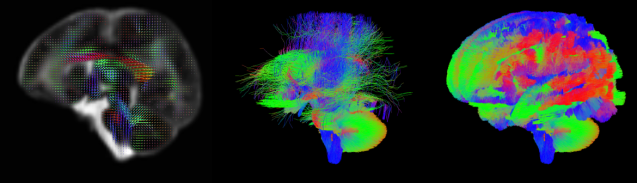

See these amazing images, for example, from the King’s College London human connectome project:

Their detailed connectome images from developing brains are stunningly beautiful, showing the incredible profusion of connections within a developing brain.

Left: Multi-shell high angular resolution diffusion data decomposed into a free water component (greyscale background image) and a directionally resolved brain tissue component shown as rendered surfaces. Middle and right: Visualisation of anatomical connections in the developing brain derived from the brain tissue component.